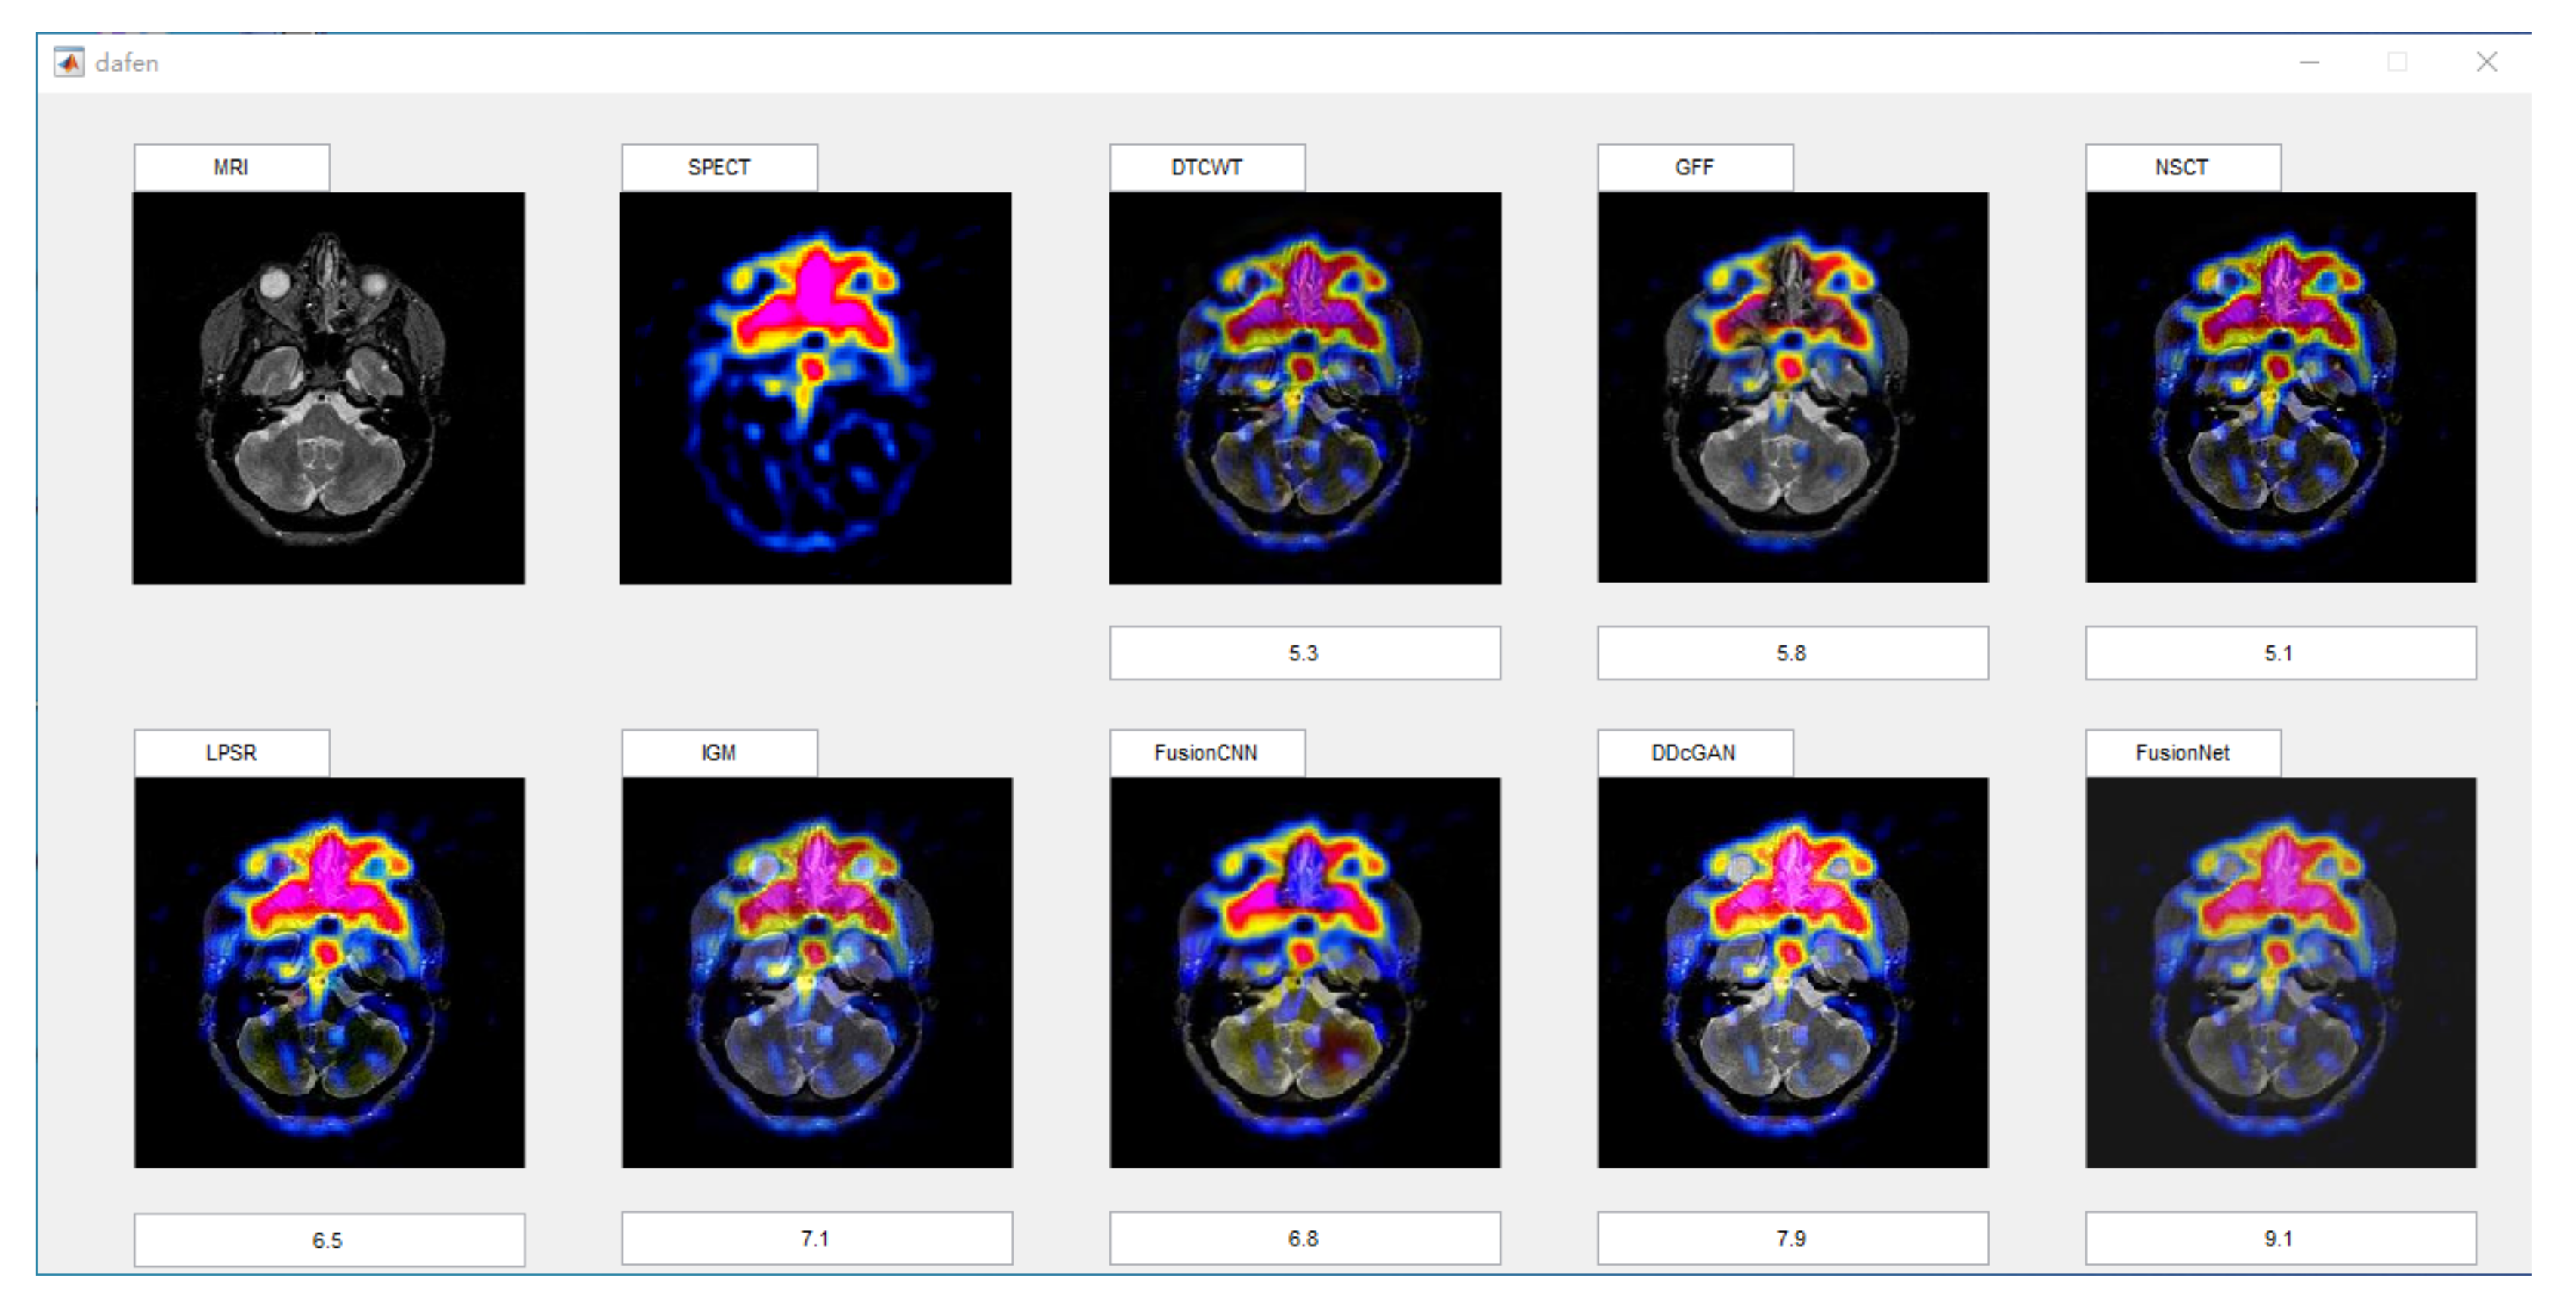

Subjective evaluation methods generally rely on doctors in the field of organizing medical imaging to evaluate the visual effects of fused images. The evaluation method is relatively reliable. After all, the evaluation results are based on the doctors’ years of experience. However, there are also differences in the scores caused by the difference between the field of personal expertise and the research direction. The objective method predicts the visual quality of the fused image by modeling the human visual system, which can avoid the disadvantages of the subjective method. However, due to the complexity of the human visual system, modeling is impossible, so the evaluation result will deviate from human judgment. In our experiment, we used the above two methods to compare our algorithm with another seven representative algorithms. In order to minimize the interference of other factors on the subjective evaluation, we selected 10 male doctors and 10 female doctors in different hospitals, all of whom were from the medical imaging department. In order to reduce the impact of the environment on them, the assessment work is carried out in the same office. All images will be displayed on the computer monitor at the same resolution, so that you can ensure that everyone sees the same quality fused image. Scoring is done on a MATLAB GUI, which provides an enlarged tool for doctors to check details. The GUI is shown in Figure 5.

Figure 5.

Interface of subjective scoring system.

Doctors could give a score between 1 and 10 based on the texture, detail, and color changes in the fused image. For each fusion image, we will calculate its average score and variance as its subjective score. In view of the fact that there are three types of our functional images in the experiment, in the corresponding three types of fused images, we will select four groups of representative fused images for subjective scoring for each type.

In this section, there are four multi-modal image sets and each set is consist of MRI image and SPECT image that are corresponding to the sanme location slice of the brain as shown in Figure 7. Among them, Figure 7e,f are captured from patients who have suffered a subacute stroke. Figure 7a–d,g,h are captured from patients who have brain tumor. The fused images with different fusion methods based on DTCWT, NSCT, GFF, LPSR, IGM, DDcGAN, FusionCNN, and the proposed methods are shown in Figure 8, Figure 9, Figure 10 and Figure 11. It can be seen that the fused images obtained by LPSR and FusionCNN algorithm have serious color distortion. Based on DTCWT and NSCT algorithm, the fusion image structure information is not obvious. The fused images obtained by GFF and IGM algorithm contain almost no color information, which is not conducive for doctors to make correct diagnosis. The image obtained by the DDcGAN algorithm saves the color information in the SPECT to a great extent; however, the brightness of the fused image is too large, which causes the image to have no sense of hierarchy and the contrast to decrease. By comparing with other algorithms, we find that our algorithm has good color retention effect, clear structure information, moderate brightness, and no artifacts.

From Figure 12 and Figure 13, we find that algorithm obtains the greatest preference, indicating that FusionNet can get better fusion results from the subjective aspect. The objective evaluation metrics of fused images of all methods in the MRI-SPECT image fusion are shown in Figure 14, Figure 15, Figure 16, Figure 17, Figure 18, Figure 19, Figure 20, Figure 21, Figure 22 and Figure 23. Our FusionNet performs well on SSIM, , , and VIF in MRI and SPECT fusion images. In terms of EN, CE, AG, and FMI, our algorithm is slightly inferior to DDcGAN, IGM, GFF, and FusionCNN. As for the remaining two indicators, our algorithm is similar to other algorithms. Subjective evaluation and objective evaluation are inconsistent sometimes; however, in medical diagnosis, objective evaluation cannot be a complete basis for diagnosis, while subjective evaluation is often more comprehensive. However, the fusion images got by FusionNet have achieved good results in subjective and objective evaluation.